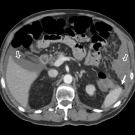

A 75-year-old man developed sharp left upper quadrant pain immediately following an esophagogastroduodenoscopy (EGD) and colonoscopy performed for persistent generalized abdominal discomfort.